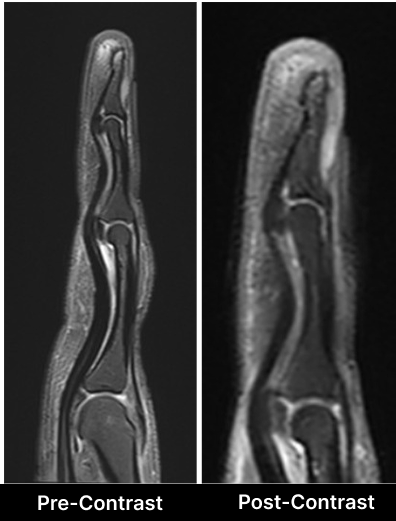

A 58 year Female presented with C/o right middle finger pain and tenderness.

Since the mass is usually very small in size, it is very difficult to palpate. Hence, MRI is the imaging modality of choice. Contrast MRI has a significant role in the diagnosis of glomus tumors.